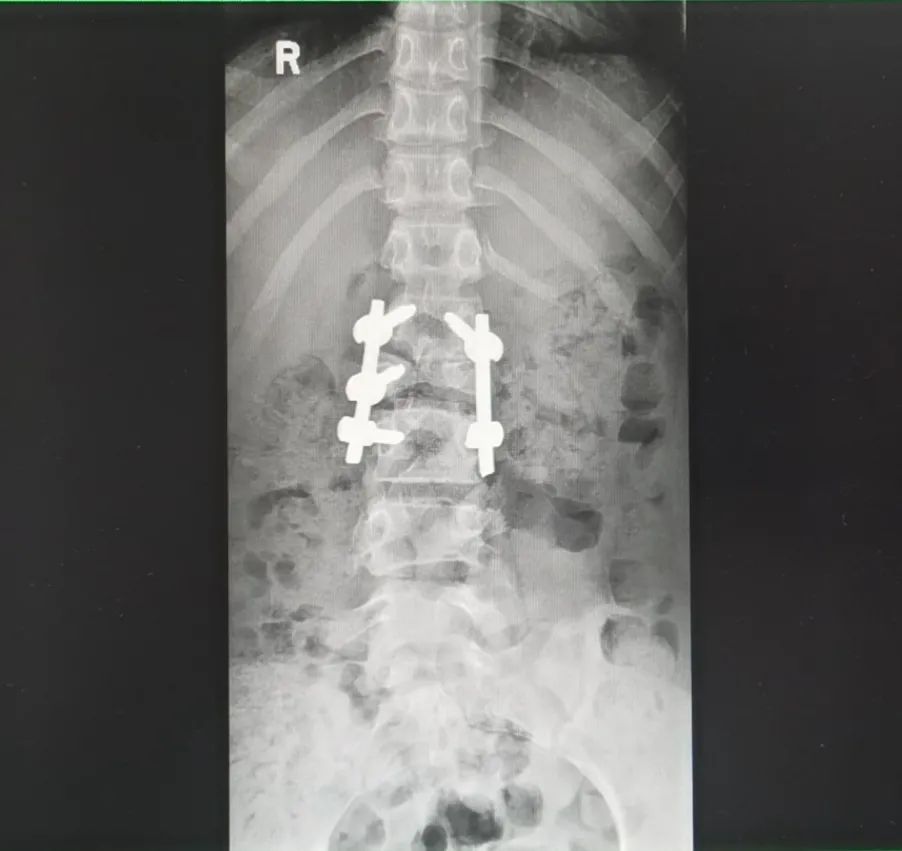

8月12日,经过充分的术前准备后,由王达义教授主刀,带领团队为小梦开展截骨矫形手术。王达义教授在先进的神经监护仪器的监护下,使用“切骨如切豆腐”的超声骨刀,根据术前计算标记好的截骨角度及节段,精准切除发育畸形的部分脊椎骨。

术后复查 CT显示,小梦原本畸形的腰椎得到彻底纠正。

据了解,此次手术过程,小梦的手术出血量仅200毫升,远低于同类型的四级截骨手术平均2000ml左右出血量。